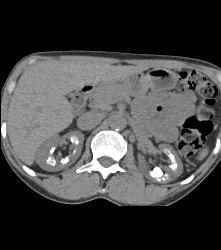

Medullary Sponge Kidney